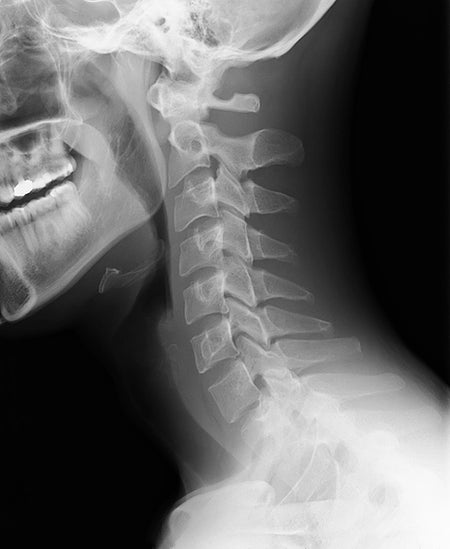

How Surgeons Reattached a Toddler's Head

Doctors saved a child who had been “internally decapitated” in a car accident. Here is the inside story